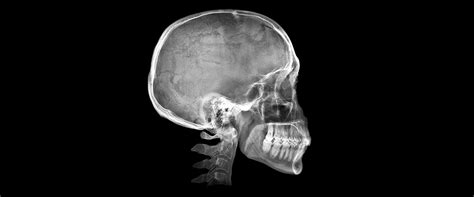

La telerradografía lateral de cráneo inicial (fig. 5) evidencia el resalte existente, con una mandíbula que presenta características típicas de tener un buen potencial de crecimiento.

Figura 5. Telerradiografía lateral de cráneo pretratamiento.

Cefalométricamente, según Ricketts (fig. 6), encontramos un patrón mesofacial, con una maloclusión esquelética de Clase II de origen mandibular, con incisivos inferiores retroinclinados.